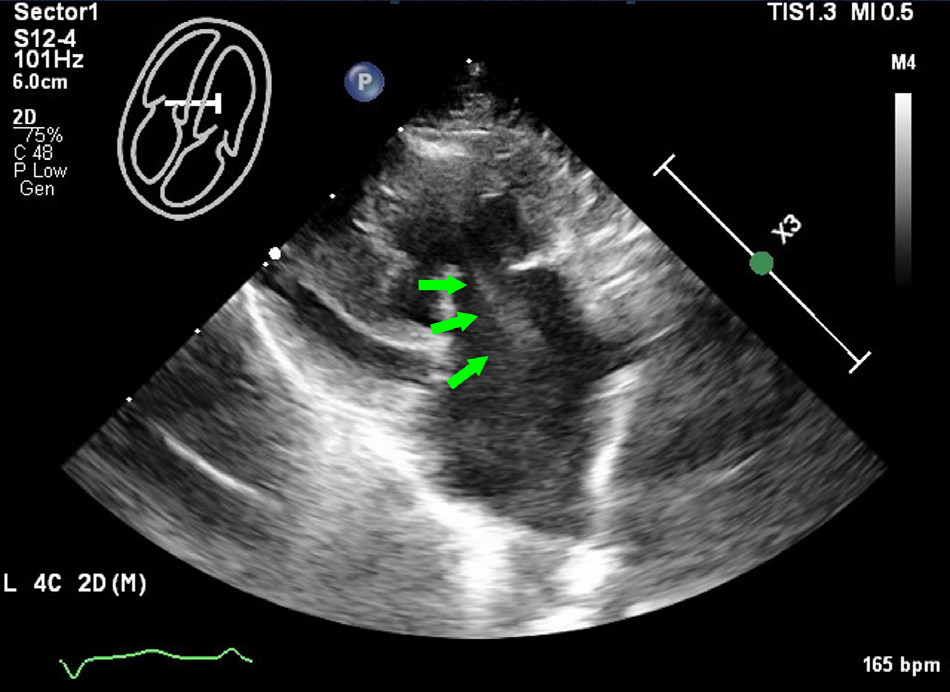

在右胸骨旁短轴视图中,前心尖壁厚度约为1.6毫米,并显示出低动力的心肌运动,符合薄壁及低动力心肌节段性心肌病的表现。在左心房中发现了自发性超声显影,表明血栓形成的风险增加(下图及视频)。

↑ B型超声心动图图像显示在左心房的左心尖四腔视图中出现自发性超声显影(绿色箭头)。

超声心动图检查发现室间隔和左心室后壁显著增厚,而心尖区域的左心室游离壁局部变薄至约1.6 mm,且心肌运动减弱,提示存在THyMS。此外,左心房收缩功能下降,左心房与主动脉比值增加,左心房内还出现了自发性超声显影,提示血栓形成风险增加。心电图显示左前分支阻滞,表现为左轴偏移,II、III和aVF导联出现小R波和深S波。